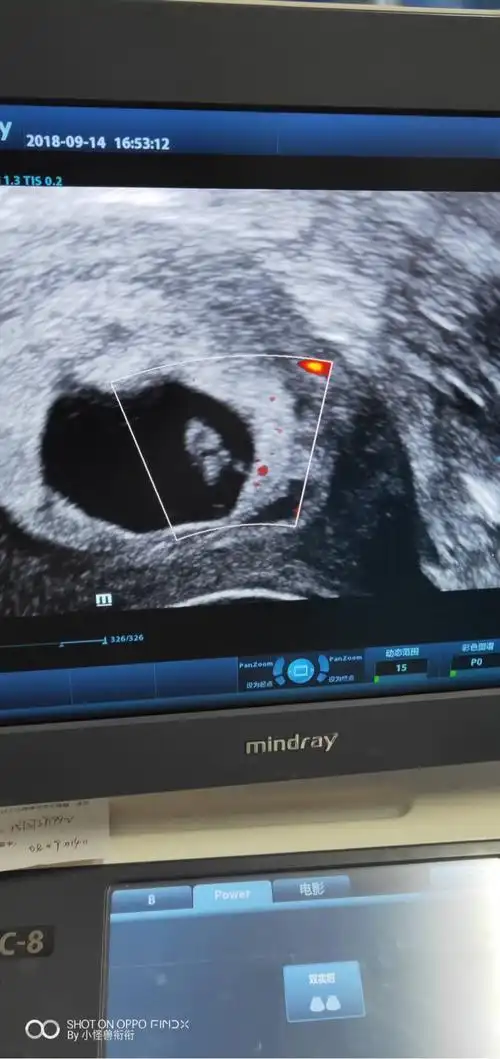

热乎乎的胎心胎芽,50天,终于放心了

胎芽3毫米还没胎心正常吗让在等一星期看看

还愿,46天见胎心胎芽